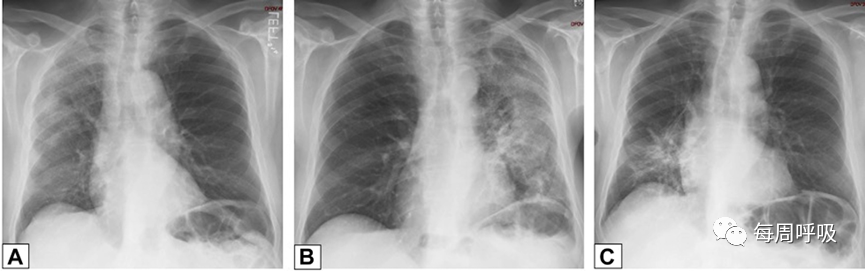

图4 OP游走性。A, 71岁男性,2011年7月因劳力性呼吸困难就诊,胸片显示右肺上叶实变。B, 2012年6月再次检查显示右肺上叶异常已消失,左肺出现广泛实变。C, 2013年6月,左肺病变消失,但右肺下叶出现新的实变。这些发现是典型的OP的游走性表现。

图5 – A-C,机化性肺炎的游走性CT表现。该患者与图4中的患者相同。